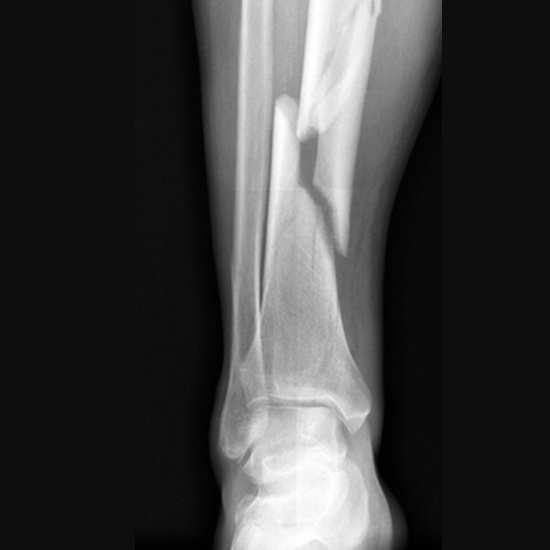

Перелом

Він буває відкритим і закритим. Для відкритого перелому характерні біль, наявність рани у місці перелому та кровотеча, неприродне положення кінцівки, хрускіт у місці перелому та уламки кістки в рані.

Закритий перелом має ті ж симптоми, проте відсутня рана. На місці перелому утворюється гематома, кінцівка збільшується в об’ємі.